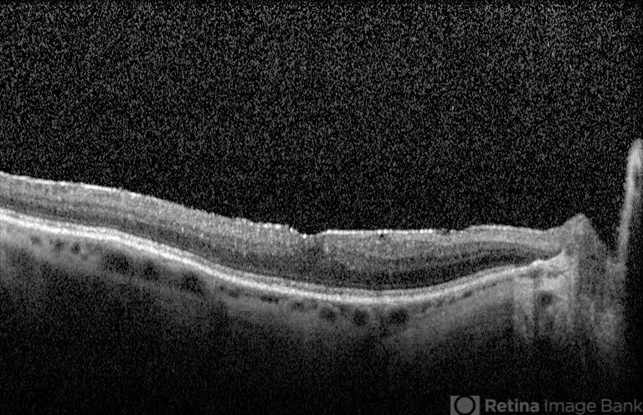

- OCT of 70-year-old male with metastatic cutaneous melanoma, 2 years after diagnosis of melanoma associated retinopathy, (MAR)